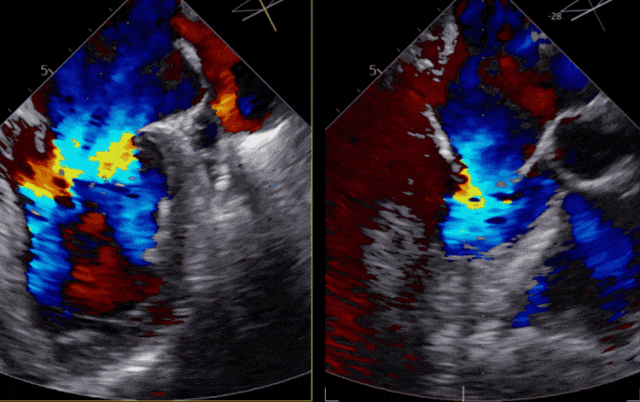

▲患者术前超声影像

患者二尖瓣3区前叶脱垂,脱垂宽度13mm,瓣口面积5.6cm2,平均跨瓣压差1.3mmHg。术前评估病人情况后决定采取策略在反流最大处植入一枚到两枚XTR或NTR,降低反流。